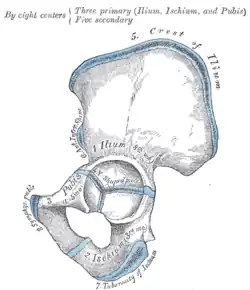

Rechtes Hüftbein. Innere Oberfläche -

Rechtes Hüftbein. Äußere Oberfläche -

Darstellung der Ossifikation eines Hüftbeines -

Beide Hüftbeine bestehen aus je drei Anteilen:

Diese drei Knochen verschmelzen beim Menschen etwa mit dem 15. Lebensjahr im Bereich der Hüftgelenkpfanne zum nun einheitlichen Hüftbein.

Alle drei Hüftknochen treffen in der Hüftgelenkpfanne (Acetabulum) zusammen, welche mit dem Kopf des Oberschenkelknochens das Hüftgelenk bildet.